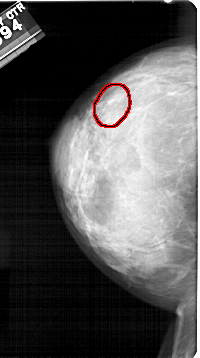

FILE: A_1326_1.LEFT_CC.OVERLAY

TOTAL_ABNORMALITIES 1

ABNORMALITY 1

LESION_TYPE CALCIFICATION TYPE PLEOMORPHIC DISTRIBUTION LINEAR

ASSESSMENT 4

SUBTLETY 4

PATHOLOGY BENIGN

TOTAL_OUTLINES 1

BOUNDARY